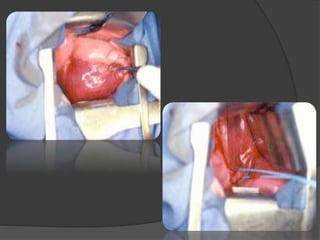

TRAITEMENT

 Traitement chirurgical +++.

 Principes: Ligature-section du vaisseau

systémique /Exérèse territoire séquestré

 SEL: exérèse sélective.

 SIL: lobectomie.

 L’embolisation des vaisseaux aberrants : ↓ ↓ ↓

les risques vasculaires.

TRAITEMENT  Traitement chirurgical+++.  Principes: Ligature-section du vaisseau systémique /Exérèse territoire séquestré  SEL: exérèse sélective.  SIL: lobectomie.  L’embolisation des vaisseaux aberrants : ↓ ↓ ↓ les risques vasculaires.